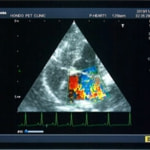

A:超音波カラードップラーでの僧帽弁逆流速度の測定

C:僧帽弁逆流の動画(大きく表示させたい場合は、ココをクリックして下さい。)